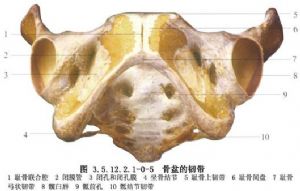

骨盆是由骶骨、尾骨和兩側髖骨(髂骨、坐骨和恥骨)連接而成的堅強骨環。兩側髂骨和骶骨構成骶髂關節。骨盆是脊柱與下肢間的橋樑,軀幹的重力通過骨盆傳遞到下肢,下肢的震盪也通過骨盆上達脊柱。骨盆並保護着盆腔內的重要臟器。

骨盆環分前後兩部分:後部是承重主弓,直立位時重力線經骶髂關節至兩側髖關節爲骶股弓(圖3.5.12.2.1-0-1);坐位時重力線經骶髂關節至兩側坐骨結節爲骶坐弓(圖3.5.12.2.1-0-2~3.5.12.2.1-0-7)。骨盆內血管十分豐富,盆壁動靜脈支緊貼盆壁而行並相互吻合成環。盆腔臟器有伴其動脈的靜脈支和異常豐富的靜脈叢(圖3.5.12.2.1-0-8,3.5.12.2.1-0-9)。後者又多圍繞盆腔內壁,且相互通連。骨盆骨折時易使鄰近的血管損傷而引起大出血,除形成盆腔血腫外,出血量大者還將沿腹膜後間隙向上擴展,形成巨大的腹膜後血腫,引起腹膜刺激症狀。此外,骨盆主要由松質骨構成,血液供應很豐富,骨折斷面可大量滲血,骨盆後壁骨折和骨盆的多發骨折尤易併發大量出血。